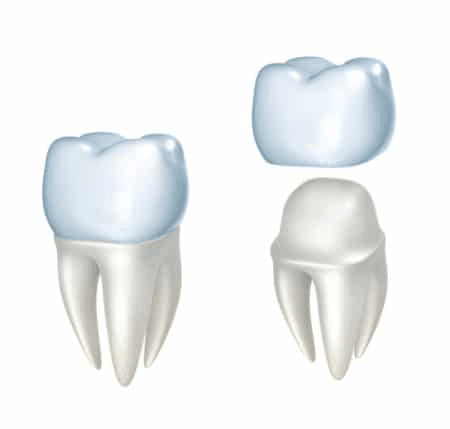

Dental crowns are custom-made restorations designed to cover and protect damaged or weakened teeth. They are often made from materials such as porcelain, metal, or a combination of both, and they restore the tooth’s shape, size, strength, and appearance.Crowns are typically used after root canal treatment, to support large fillings, or to improve the cosmetic appearance of a tooth. By providing a durable solution, dental crowns can help enhance oral function and maintain overall dental health.

What Is a Dental Crown?

A dental crown is a clinical procedure that plays a key role in restoring and protecting compromised teeth. It involves placing an external cap over the tooth to restore its strength and shape. This procedure offers an effective solution to prevent further damage and to improve the cosmetic appearance of the teeth.Dental crowns are used in multiple situations, including: